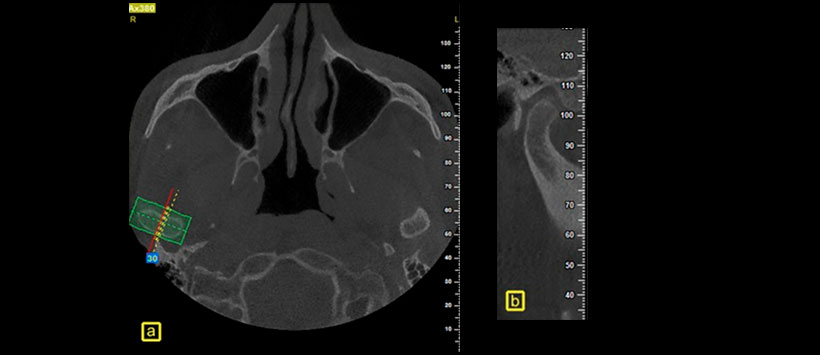

Para lo cual se evaluaron los datos de CBCT de ATM bilaterales de 40 pacientes con TMD y 23 casos sin síntomas (Figura 1). Se midieron la inclinación de la eminencia articular (Figura 2), así como la profundidad (Figura 3) y el ancho de la fosa glenoidea de la fosa mandibular (Figura 4). Obteniendo como resultado que la inclinación de la eminencia articular, la anchura y profundidad de la fosa glenoidea fueron significativamente mayores en los pacientes con TMD que en el grupo control. La inclinación de la eminencia articular fue más pronunciada en pacientes con TMD que en el grupo control. El ancho y la profundidad de la fosa glenoidea fueron mayores en los pacientes con TMD que en el grupo control. Esta información puede arrojar luz sobre la relación entre la morfología de la ATM y la incidencia de TMD.